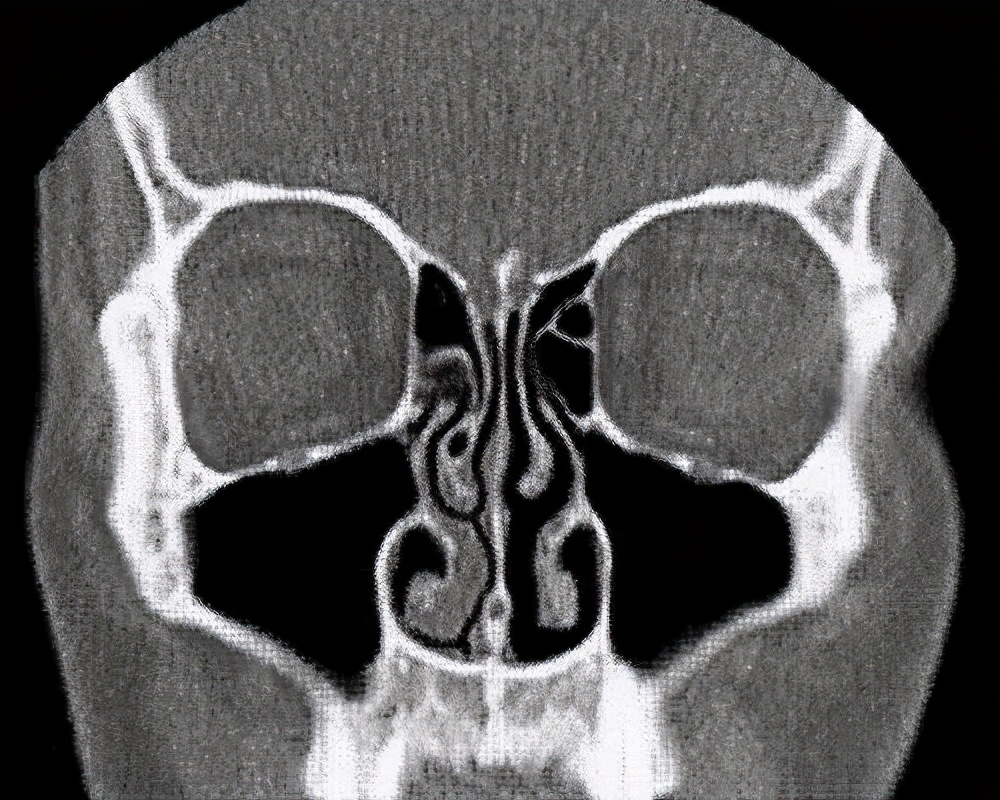

(CT扫描时的鼻周期,左侧的呼吸道堵塞,右侧的呼吸道畅通)

一般情况下,一个鼻周期大约为2小时~7小时。所以说,一天之内能发生好几个鼻周期。